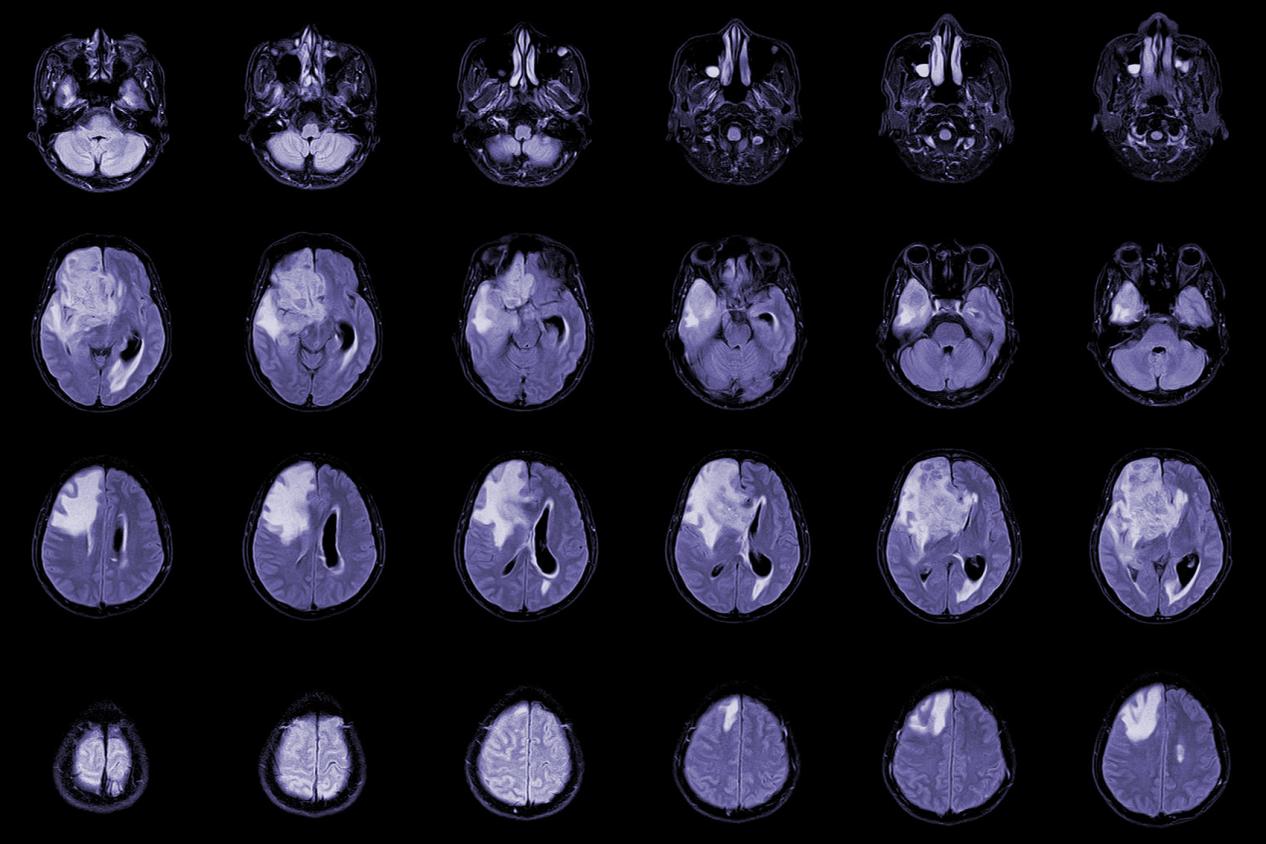

脑胶质瘤放射治疗效果,昆明脑胶质瘤医院哪家好-昆明医科肿瘤医院脑胶质瘤是一种恶性的脑部肿瘤,通常需要进行综合治疗,其中放射治疗是一种重要的治疗手段。本文将介绍脑胶质瘤放射治疗的基本原理、应用情况、不良反应及注意事项等方面。一、放射治疗的原理脑胶质瘤放射治疗是利...

脑胶质瘤早期症状,昆明脑胶质瘤筛查医院哪家好-昆明医科肿瘤医院脑胶质瘤是指起源于脑胶质细胞的肿瘤。脑胶质细胞是脑部最常见的一种细胞,主要负责支持和保护神经元。然而,当这些细胞发生异常增殖和变异时,就会形成脑胶质瘤。脑胶质瘤可以分为良性和恶性两种类型。良性脑胶质...